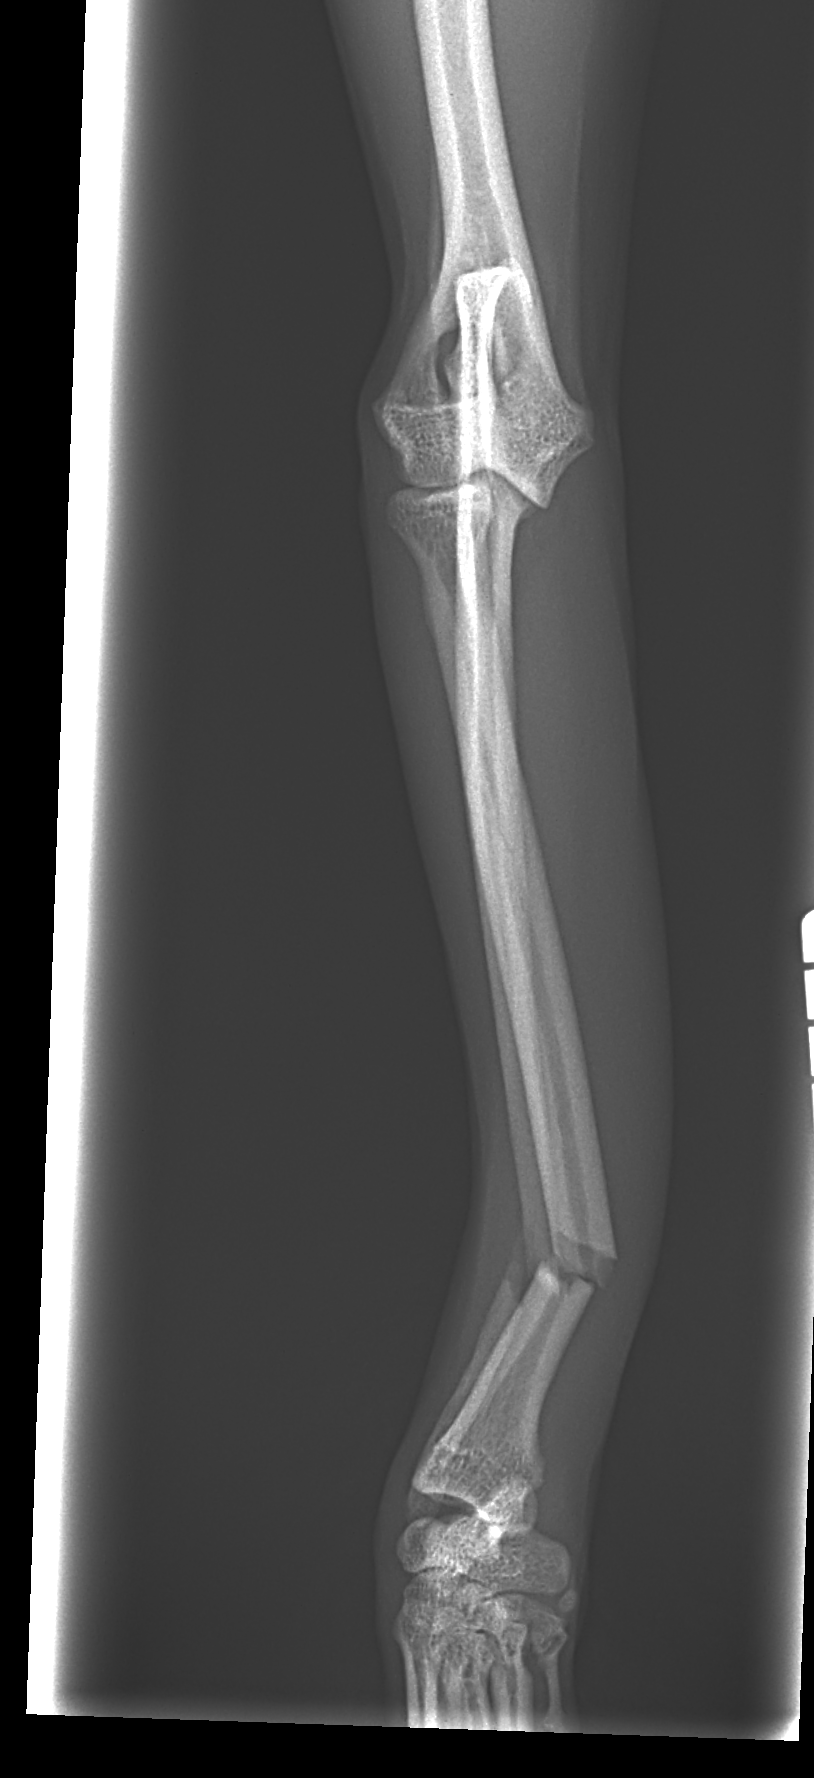

橈骨固定術 #249 Toy Poodleさんがソファーからジャンプして橈骨骨折をしたとのことで主治医の先生から固定術の依頼がありました。1.5 Titanium Locking Plateで固定術を行いました。しばらくは安静が必要です。 症例カテゴリー 放射線治療整形外科軟部組織外科脳神経外科内科腫瘍外科救急・集中治療リハビリテーション科腫瘍内科内視鏡科脳神経科呼吸器外科中医・漢方猫の腎移植循環器科